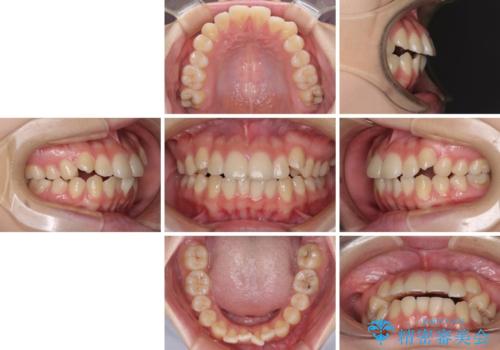

カリエール・ディスタライザーとインビザラインを用いた八重歯の改善

- 前歯の叢生と上顎左右の八重歯を気にして来院された患者様です。

奥歯の咬み合わせを見ると、左側は上顎が下顎に対して相対的に前方にあり、上下の前歯が接触していない状態でした。

咬み合わせを改善するためには、左側上顎臼歯を後方に移動させた咬み合わせにする必要があります。

インビザライン単体で改善することも可能性もありますが、インビザライン単体で達成する可能性が低いと考えられたため、カリエール・ディスタライザーという補助装置を併用して、より確実性を上げることとしました。

奥歯の咬み合わせを改善しながら、並行してインビザラインで歯列を整えることとしました。

カリエールディスタライザーを併用したことで、左側臼歯の咬み合わせを確実に改善させることができました。